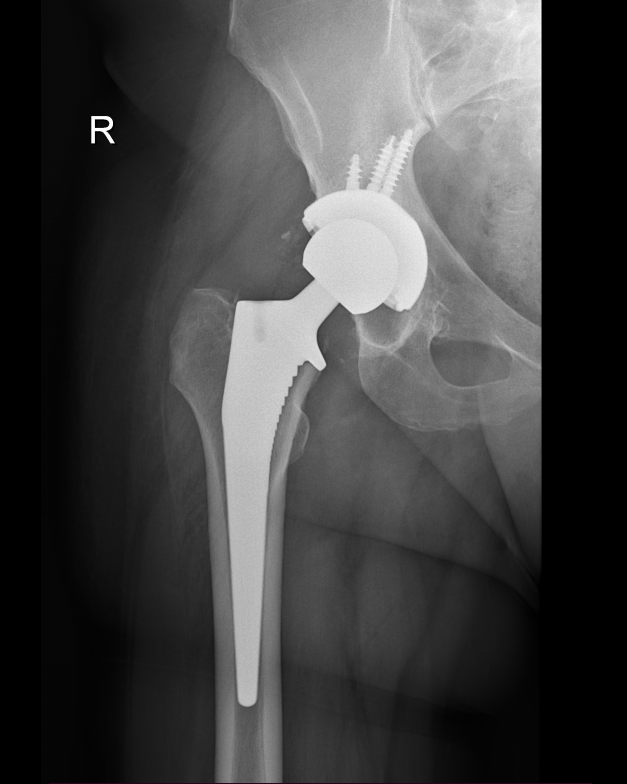

Diagnosis is made by evaluating medical history, physical examination and X-rays.

The surgery is performed under general anesthesia. During the procedure a surgical cut is made over the hip to expose the hip joint and the femur is dislocated from the acetabulum. The surface of the socket is cleaned and the damaged or arthritic bone is removed using a reamer. The acetabular component is inserted into the socket using screws or occasionally bone cement. A liner made of plastic, ceramic or metal is placed inside the acetabular component. The femur or thigh bone is then prepared by removing the arthritic bone using special instruments, to exactly fit the new metal femoral component. The femoral component is then inserted to the femur either by a press fit or using bone cement. Then the femoral head component made of metal or ceramic is placed on the femoral stem. All the new parts are secured in place using special cement. The muscles and tendons around the new joint are repaired and the incision is closed.